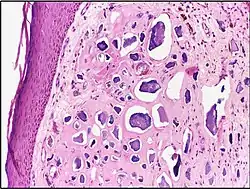

| Micrograph of calcinosis cutis. The calcification is purple (bottom of image). H&E stain. | |

Calcinosis cutis is a type of calcinosis wherein calcium deposits form in the skin. A variety of factors can result in this condition. The most common source is dystrophic calcification, which occurs in soft tissue as a response to injury. In addition, calcinosis is seen in Limited Cutaneous Systemic Sclerosis, also known as CREST syndrome (the "C" in CREST). In dogs, calcinosis cutis is found in young, large breed dogs and is thought to occur after a traumatic injury.